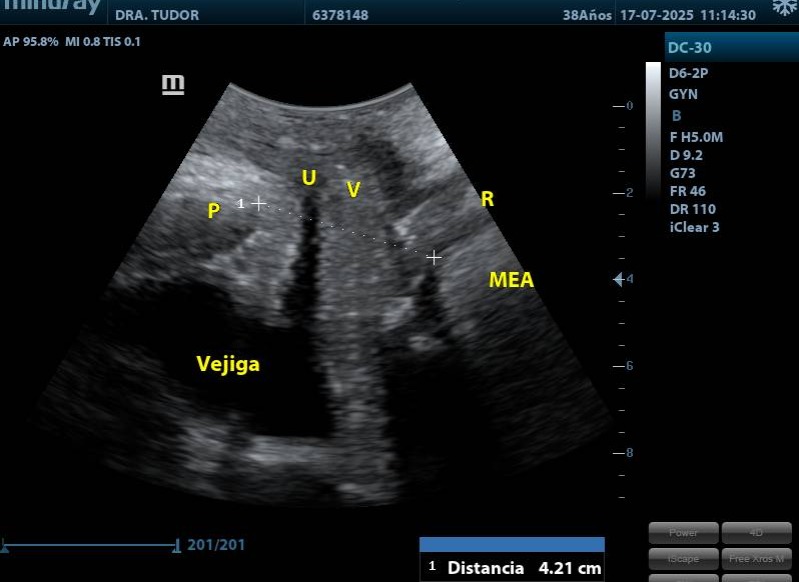

ECOGRAFIA DE PISO PELVICO

■ Diagnóstico de prolapsos (cistocele, rectocele, histerocele, enterocele). Hacer la diferenciación y evaluar los grados.

■ Diagnóstico diferencial de disfunción miccional o del tracto de salida.

■ Seguimiento posquirúrgico.

■ Complementaria a la exploración física y urodinámica.